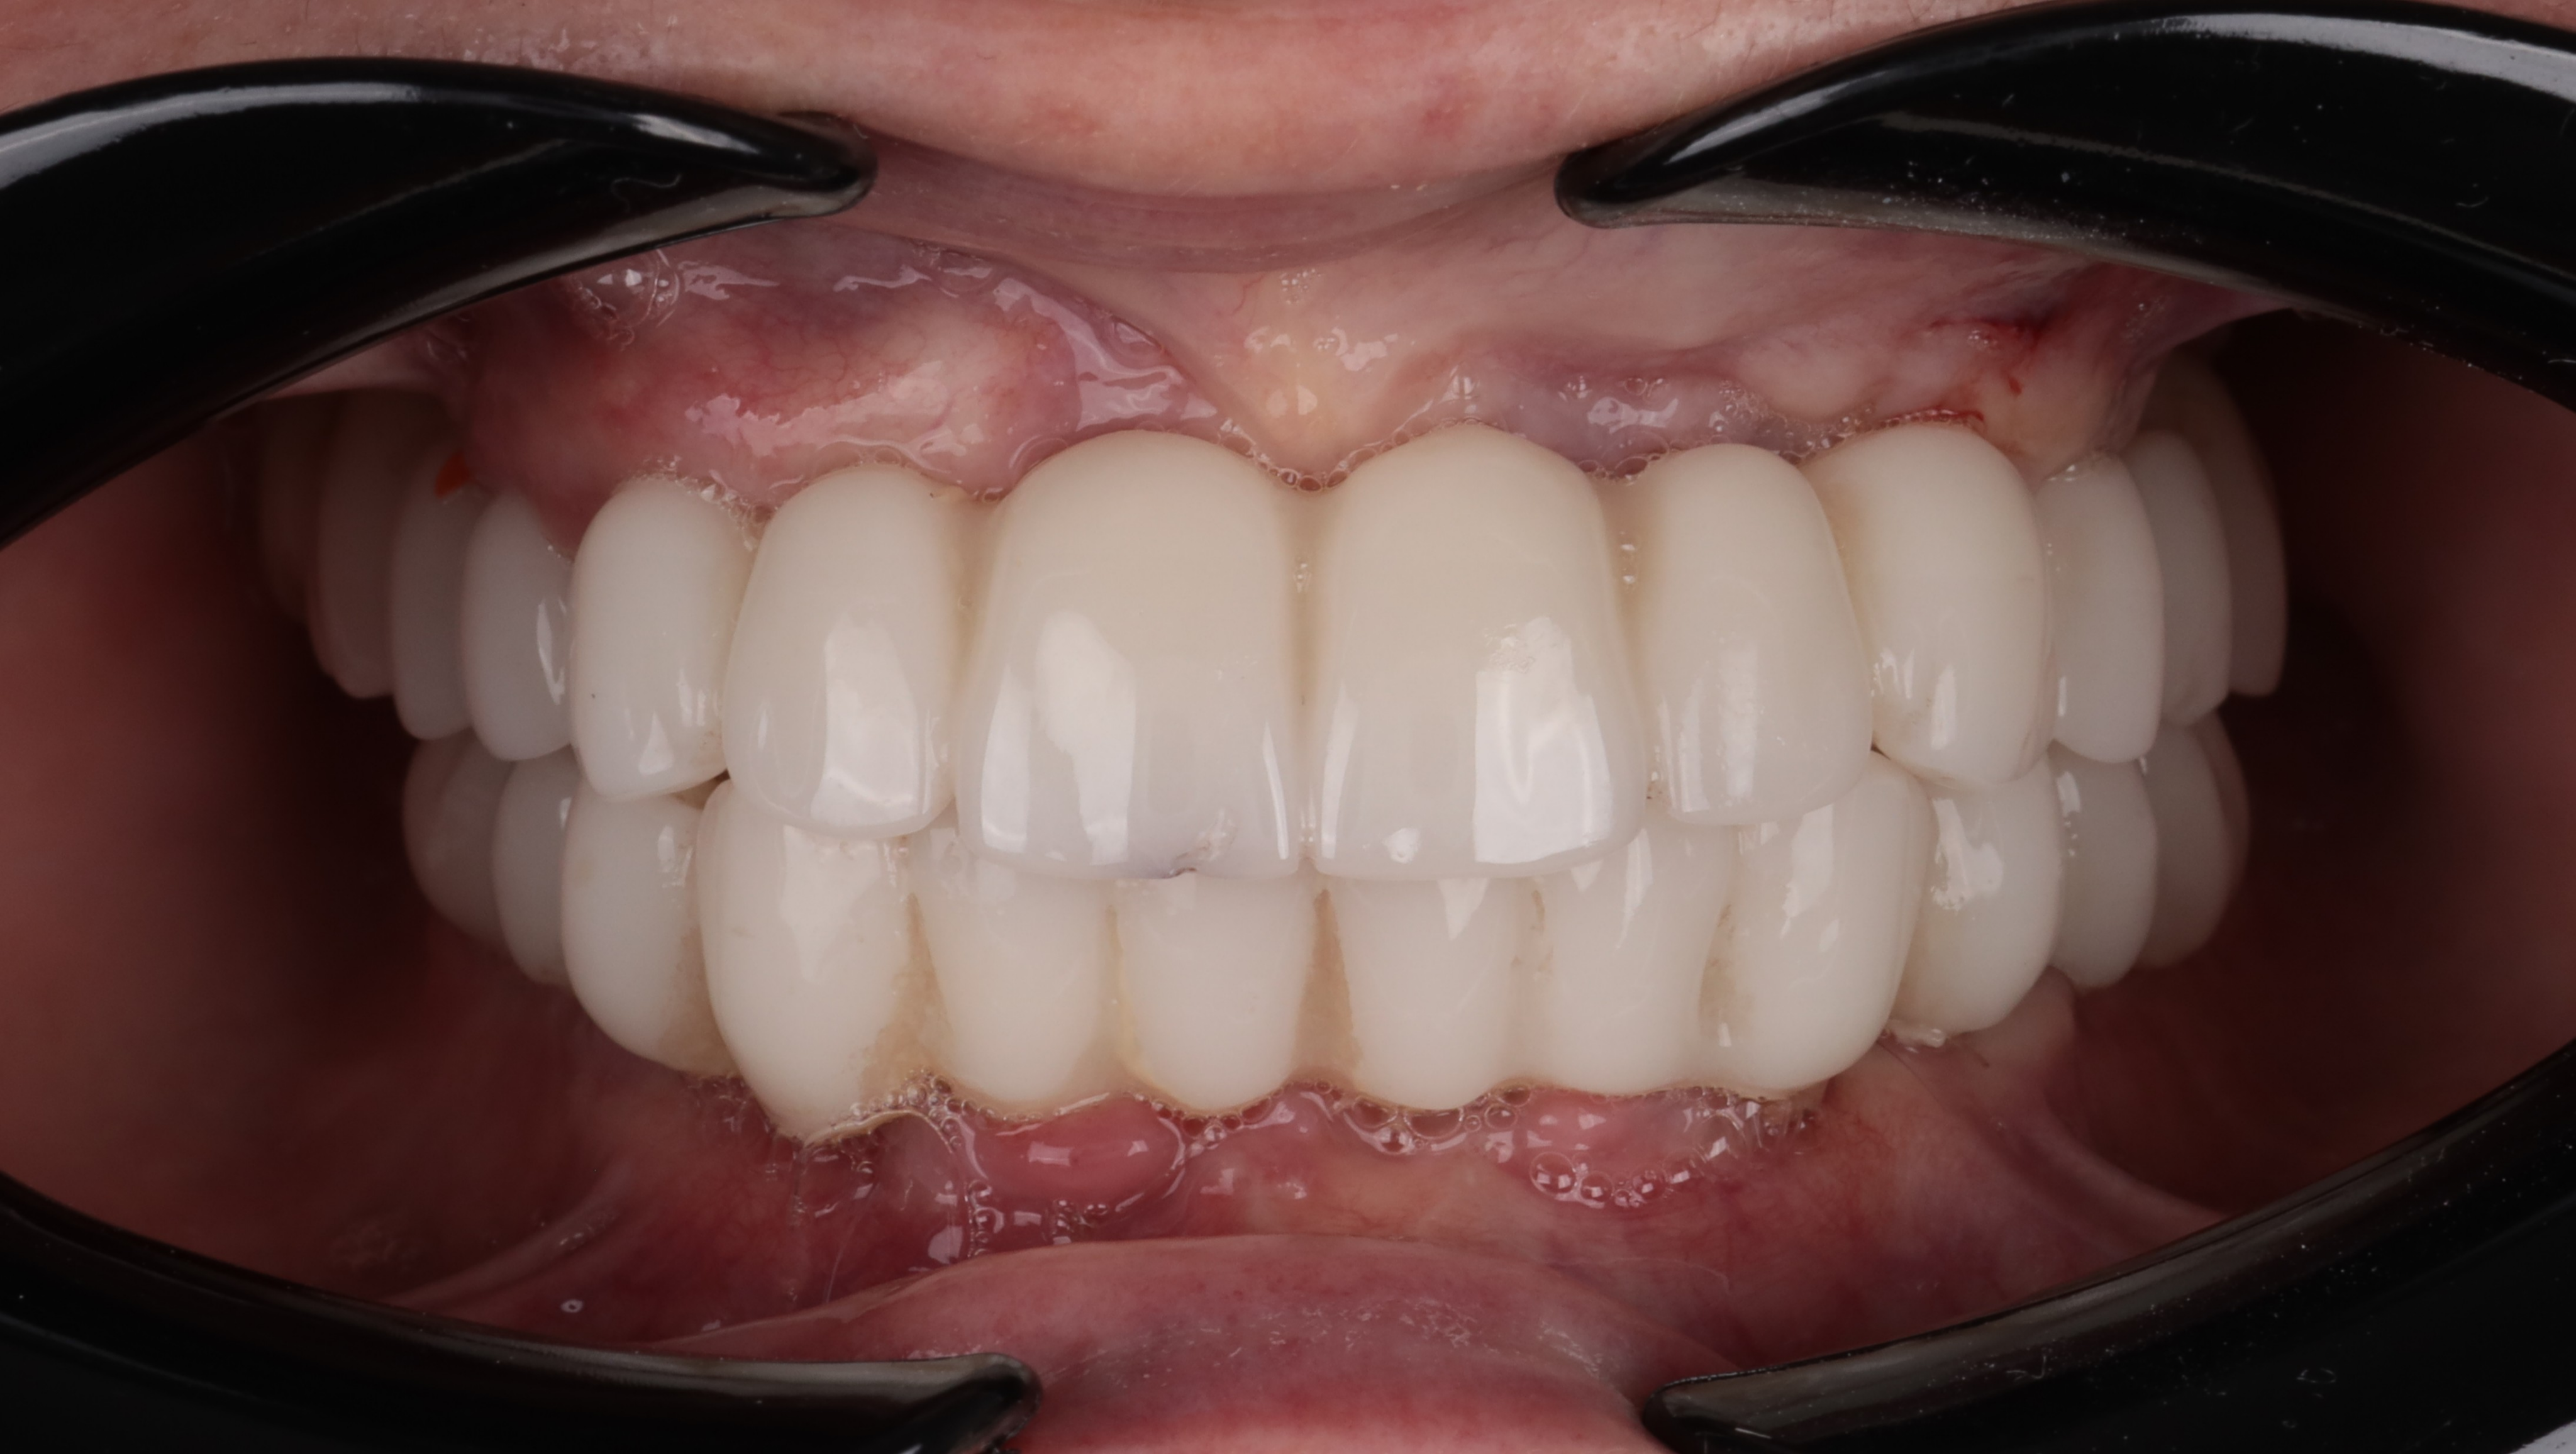

At the six-month follow-up, the patient reported high satisfaction with the functional and aesthetic performance of the provisional restorations. Clinical examination following the removal of the provisionals revealed optimal soft tissue healing and well-preserved gingival architecture. Notably, the Root Shield sites at 13, 12, and 23 successfully maintained the buccal ridge contour, while radiographic evaluation (OPTG) confirmed complete osseointegration of all implants, including the pterygoid fixtures at sites 17 and 27.

The final restorative phase utilized a repeat IPG scan to ensure micron-level accuracy for the definitive frameworks. The maxilla was restored with a zirconia bridge on a titanium framework, while a metal-composite framework was selected for the mandible. The definitive prostheses achieved a perfect passive fit and optimal seating, successfully restoring both masticatory function and the patient’s natural aesthetic smile.